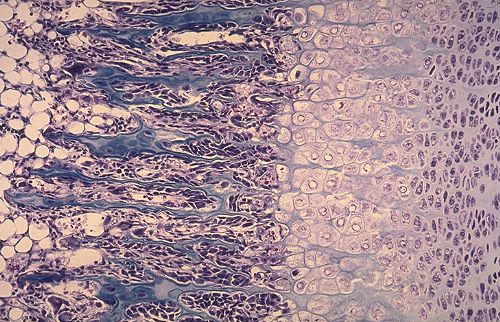

--> Les chondrocytes s'empilent et forment des "colonnes de groupes isogéniques" de manière à constituer un "cartilage de type sérié".

Mais j'ai remarqué que ça ressemble à la croissance interstitielle du cartilage quand les chondrocytes s'alignent en colonnes et formes des groupes isogéniques axiaux.